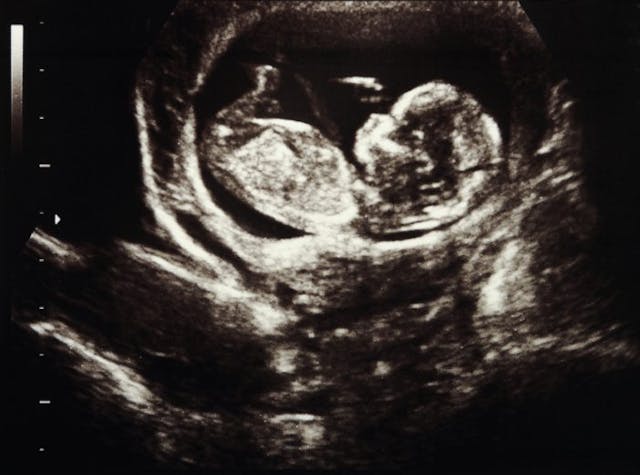

Six in 10 Centers Offer Free Ultrasounds

Offering each woman and her family the chance to meet their newest member in utero, six out of every 10 pregnancy centers in the U.S.—1,661 total—serve women with free limited obstetric ultrasounds.

While it’s impossible to definitively pinpoint the effectiveness of an ultrasound (given the complexity and uniqueness of each woman’s journey through an unexpected pregnancy), mothers like Kelsey say they decided against abortion the moment they met their child through an ultrasound at a pregnancy center.

“It was an indescribable moment for me,” Kelsey said. “I believe it was the moment I unconsciously decided I could never get an abortion.”

A Total of 248,832 Free Ultrasounds

Up 10 percent from a 2011 study by the Family Research Council, pregnancy centers in the U.S. combined to deliver 248,832 ultrasounds in 2016—a number that is continuing to rise as more centers add ultrasound services.

Performed to confirm a viable pregnancy, every ultrasound at a pregnancy help medical clinic is free to clients, with donors covering nearly all costs involved.